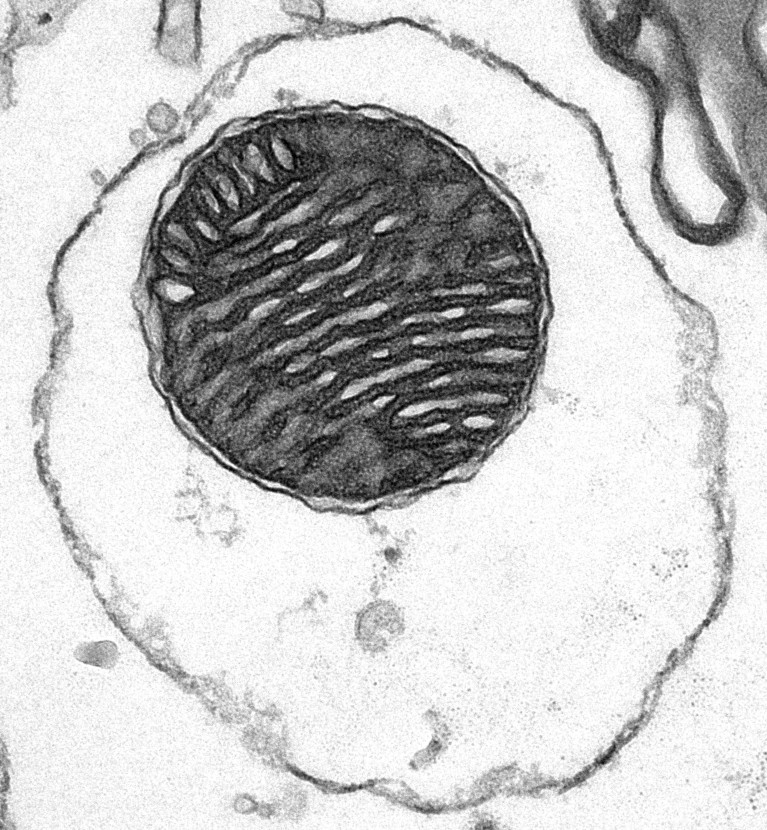

A ‘capsule’ of mitochondria (central dark circle) is enclosed by a red blood cell’s membrane (outer dark oval).Credit: S. Du et al./Cell

The authors of the Cell study settled on using the membranes of red blood cells because the cells lack organelles with their own membranes. Creating the mitochondrial ‘capsules’ was then as simple as mixing ruptured red blood cells and mitochondria isolated using a commercially available kit. The scientists then injected these ‘capsules’ into mice.

The “shell” preserves the mitochondrion’s electrical gradient, says co-author Qi Long, a biologist at Guangzhou Medical University in China. That allowed the organelles to slip into recipient cells undetected.

Using previous methods, less than 5% of cells growing in laboratory dishes absorbed the mitochondria, says co-author Xingguo Liu, a biologist at the Guangzhou Institutes of Biomedicine and Health in China. “Our efficiency is super high,” he says. “It’s around 80%.”